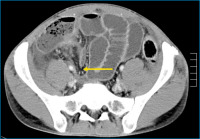

Ileum

Abbildung 4: Computertomographische Darstellung eines längerstreckigen entzündlichen Verschlusses des terminalen Ileums (Pfeil) mit prästenotisch dilatiertem Dünndarm und einer geringgradigen Koprostase im Zökum. Nebenbefundlich finden sich erneut Residuen des klinisch remittierenden Mb. Bechterew.

Keywords: ComputertomographieCTIleumMorbus BechterewZökum